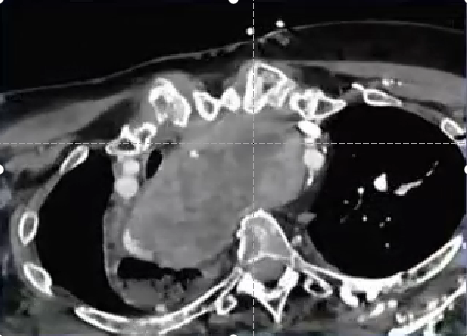

Thyroid artery embolization for Goiter reduction,TAEGR 甲状腺肿大减容动脉栓塞

甲状腺肿大

病因:不是癌症,但5%会含有甲状腺癌(PMID 31542786)